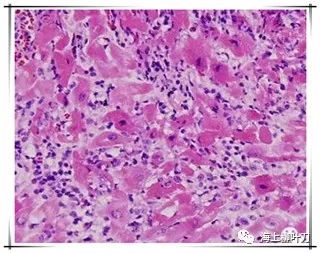

6.這是她的心肌病理切片,放大了100倍。

7.100倍還不是看得很清楚,放大400倍就很明顯了,一個個藍點就是淋巴球。這是很厲害的猛暴性心肌炎,整個心臟都被淋巴球浸潤了。